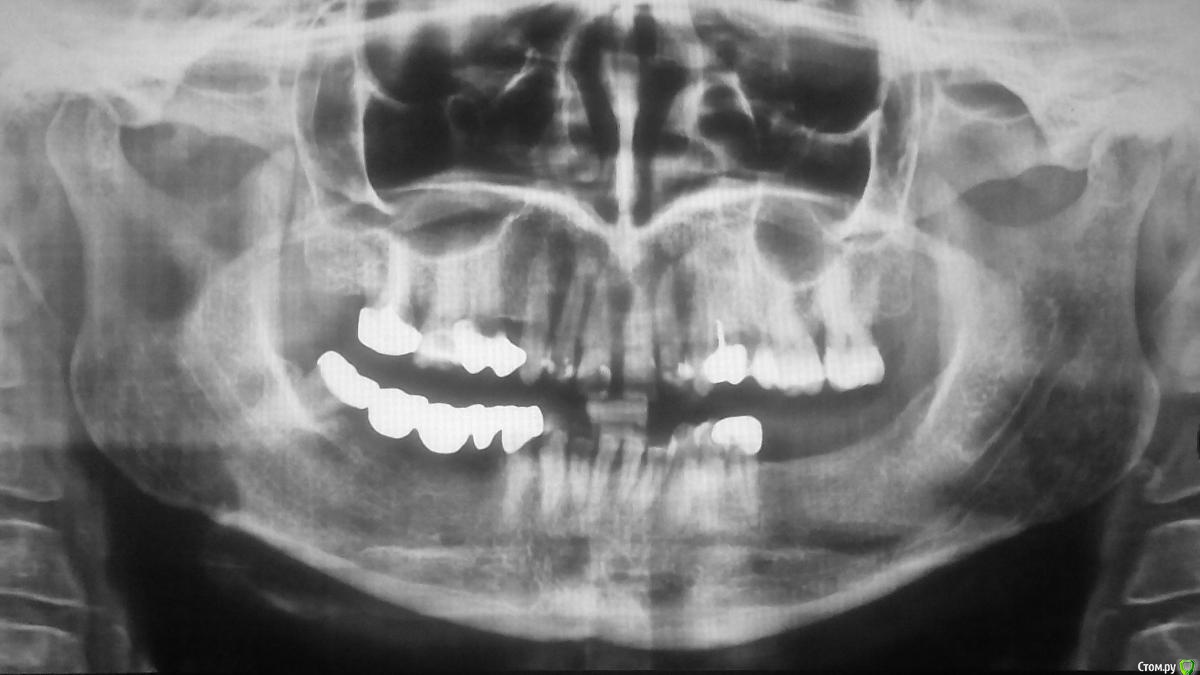

Андрей+ Опубликовано 5 ноября, 2018 Поделиться Опубликовано 5 ноября, 2018 Здравствуйте, уважаемые форумчане!Прошу вас поделиться мнением. Предупреждаю сразу: я в стоматологии ни разу не спец, потому всё, что вы скажете, может быть использовано против вас :-)Итак:Пациентке 48 лет. Передние верхние зубы (единички и двойки) лет 5-7 назад постепенно начали заметно выдаваться вперёд, зазор между единичками увеличился. При этом клыки и зубы за ними стоят примерно на том месте, где были 27 лет назад (см. фото "27"). Для полноты картины: слева 4-й зуб удалён, на 5-м коронка (ей 19 лет). Справа на 4-м коронка на штифте (штифт ставили 18 лет назад, коронку меняли 7 лет назад). Прилагаю панорамный снимок весны 2015-го года (см. фото "2015").Стоматолог предложил все верхние зубы по 5-й включительно спилить и поставить общий протез на 10 зубов, чтобы не дать выдающимся вперёд зубам продолжить движение.Вопросы:1. Предложенное доктором - поможет остановить движение зубов вперёд? Ведь корни спиленных зубов так и будут смотреть вперёд, и при давлении нижних зубов на "приклеенные" коронки усилие будет работать как на продолжение подъёма корней спиленных зубов, так и на вытягивание из челюсти корней крайних зубов моста - пятёрок. В стоматологии не силён, потому за возможную глупость в предыдущем предположении прошу снисхождения.2. Нервы в спиливаемых зубах удалять стоматолог не планирует. Нормально ли это? Ведь, воспались не дай бог нерв в одном из зубов под мостом, для удаления воспалённого нерва придётся снимать весь мост, т.е. его выбросить = заплатить за новый мост. Если каждый зуб под мостом лечить с выбрасыванием моста - никаких денег не хватит)))3. У пациентки уже лет 5 пощёлкивает (иногда с болью) левый челюстной сустав. Может ли это пощёлкивание означать смещение нижней челюсти назад, и может ли это смещение в свою очередь стать причиной выдвижения передних зубов вперёд? Т.е. не стоит ли перед установкой моста (или установкой брекетов) решить возможную проблему в челюстном суставе?4. Можно ли остановить и обратить вспять - вернув нормальный прикус - движение зубов вперёд, установив брекеты? Или в возрасте 48 лет брекеты бессильны?Буду очень признателен за ответы.С уважением,Андрей P.S. Если ошибся разделом - прошу модератора переместить мою тему в нужный. Не могу сообразить, куда постить: в "ортодонтию" или в "протезирование". Ссылка на комментарий